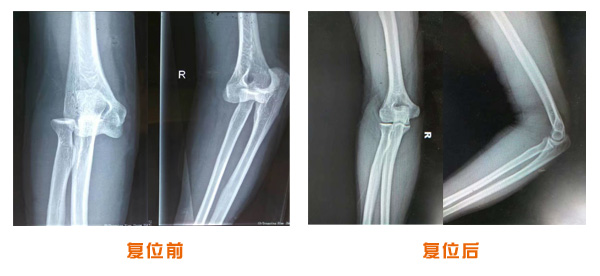

肥城市安駕莊梁氏骨科醫(yī)院是一所以梁氏手法正骨配合膏藥為特色的現(xiàn)代化專科醫(yī)院。

梁氏骨科術(shù)始創(chuàng)于清雍正年間,歷經(jīng)八代,至今已有三百年歷史。據(jù)1929年泰安縣志載“梁瑞圖先生,字增生,號蓮峰,安駕莊人,精岐黃并發(fā)明接骨,凡跌打車凡跌打車軋皮不破而碎骨者......【詳細(xì)】 |